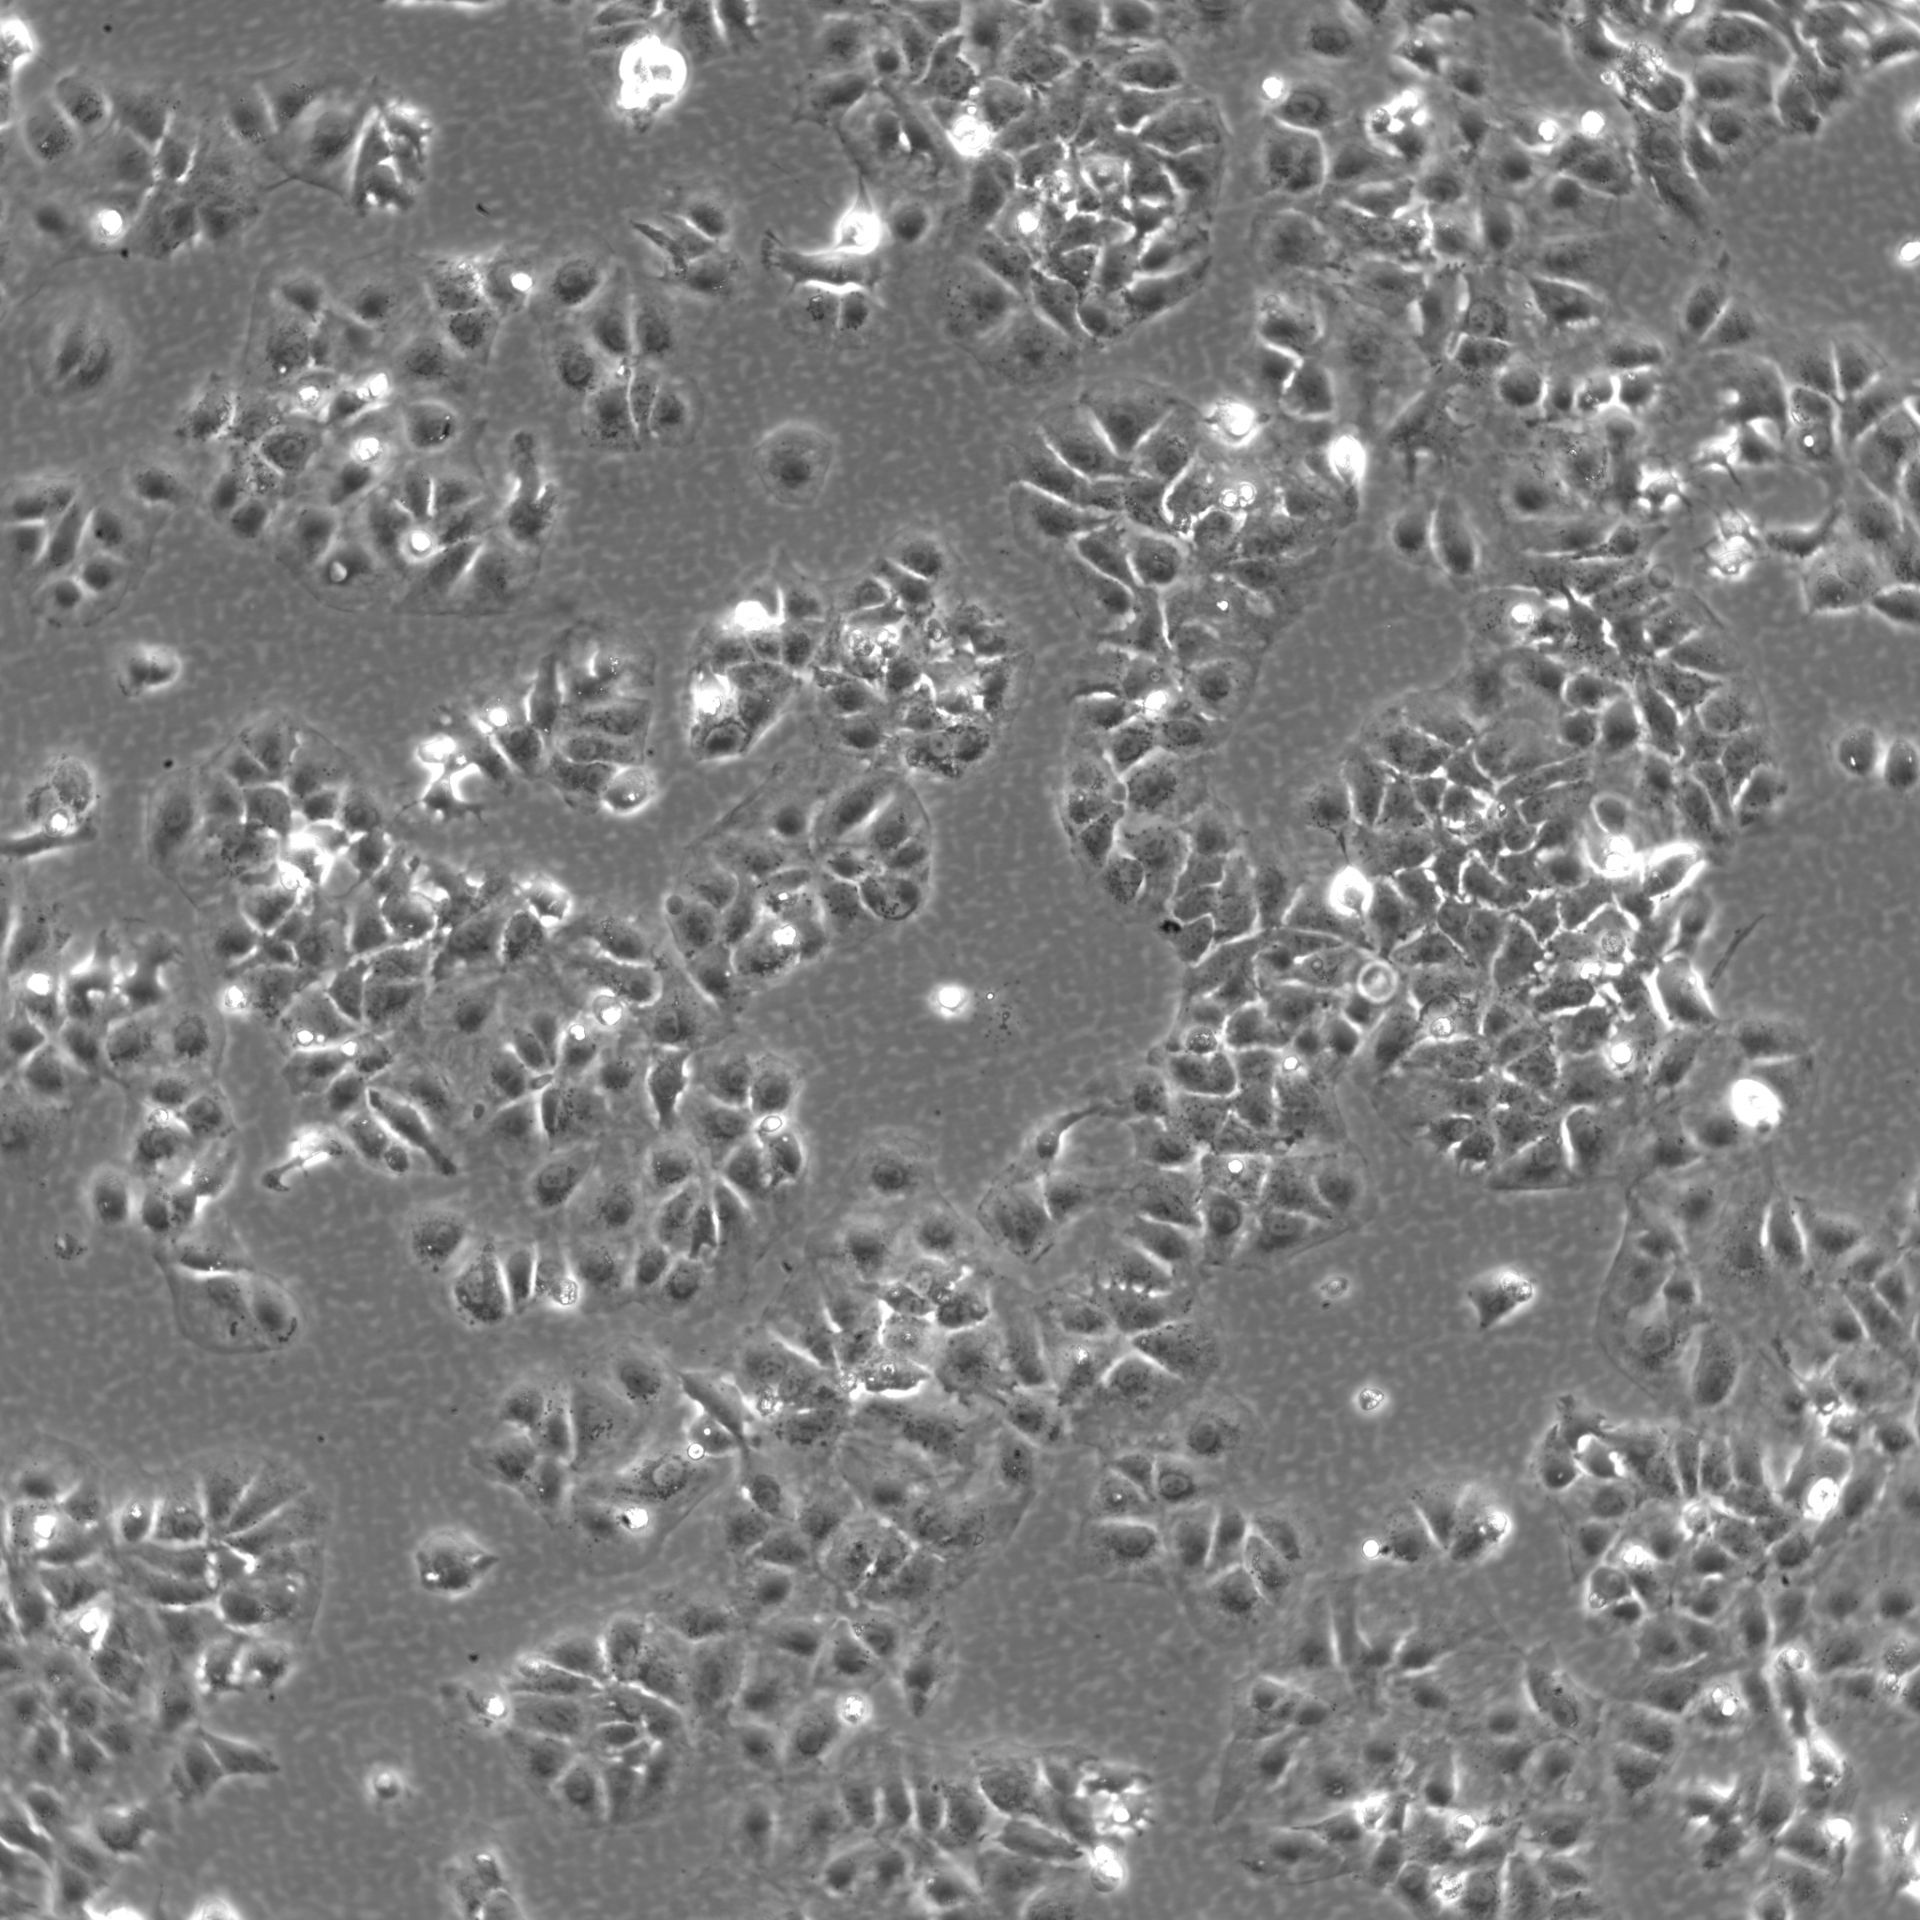

Morphology: Epithelial-like

Growth Properties: Adherent

Description: HuH7 was established in 1982 by Nakabayashi et al. from a 57-year-old Japanese male with well differentiated hepatocellular carcinoma.